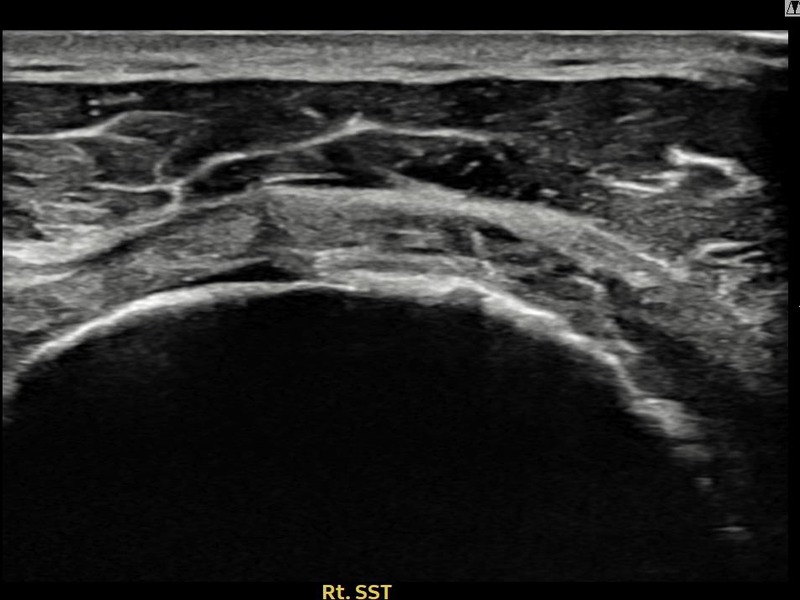

최ㅇㅇ님 · 우측 극상근건 관절면측 부분파열

우측 어깨 통증으로 수면과 일상 동작이 어려워 내원하셨습니다. 초음파 유도 하 축소봉합술 후 힘줄 연속성이 회복되었습니다.

상세 보기 →